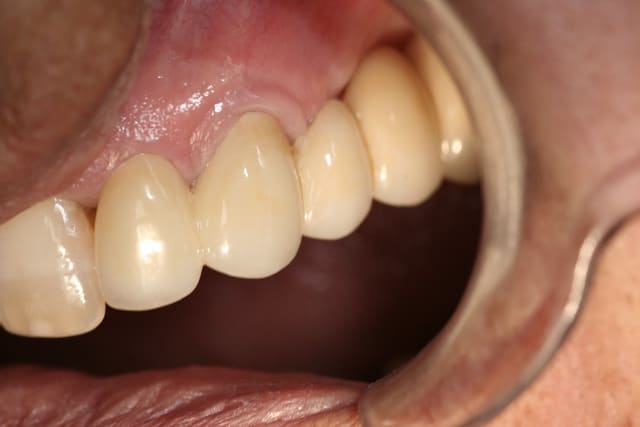

Je crois qu'effectivement la CAO peut être chiante, moi ça m'éclate. Il y a du boulot pour toutes les préférences et le travail de molinarius réunit le meilleur des deux mondes.

c'est du beau travail jumpingjack !

oui c'est du beau travail ..

Cependant je suis sure que ces types de cas ne se réalisent pas en deux temps trois mouvements!

il y du temps d'usinage , beaucoup de modelage pour parvenir à de tels cas et autant pour la finition .. donc on en revient toujours au même .. le temps que vous passez dessus vous ne le passez pas au fauteuil ...secu ou pas , votre rentabilité est ailleurs..

Sur le 1er cas de jump.... reconstitution au maxillaire , il y a plusieurs usinage(quelques heures) et un certain de temps finition à la pièce à main ... et sur d'autre plusieurs cuisson de maquillage sans doute ...

Que certains prats soient doués à jouer les prothésistes ;) c'est une chose mais je suis sure que c'est plus par plaisir de faire de la prothèse :) plutôt qu'un intérêt financier ... je me trompe jumpingjackflash ?